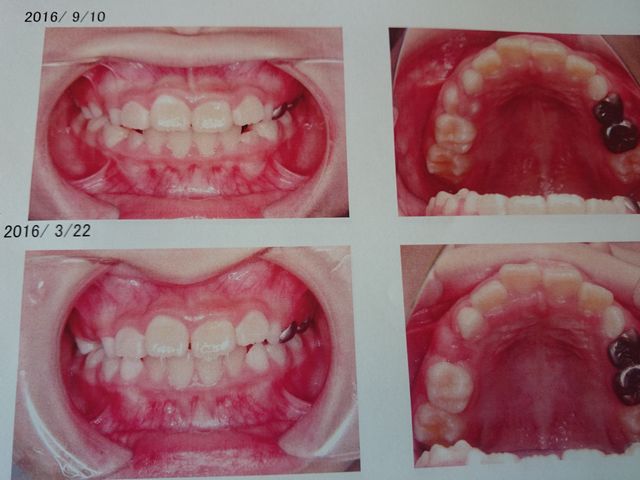

矯正歯科に行きました。二人とも少しずつよくなっています。《とり》は上の前歯四本につけていたワイヤーを外しました。

矯正しているので、だんだんきれいになってきています。